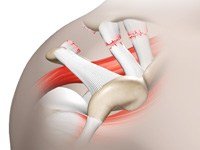

Rotator Cuff Repair

Rotator cuff is the group of tendons in the shoulder joint providing support and enabling wider range of motion. Major injury to these tendons may result in tear of these tendons and the condition is called as rotator cuff tear. It is one of the most common causes of shoulder pain in middle aged adults and older individuals. It may occur with repeated use of arm for overhead activities, while playing sports or during motor accidents.